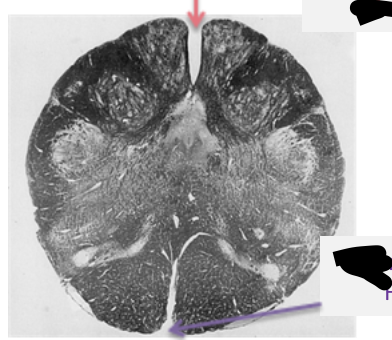

What level cut of the brainstem is this?

What does the cross section of caudal pons (CN VII) look like?

What cross section is this? What does it kind of look like?

What brain stem cut is this?